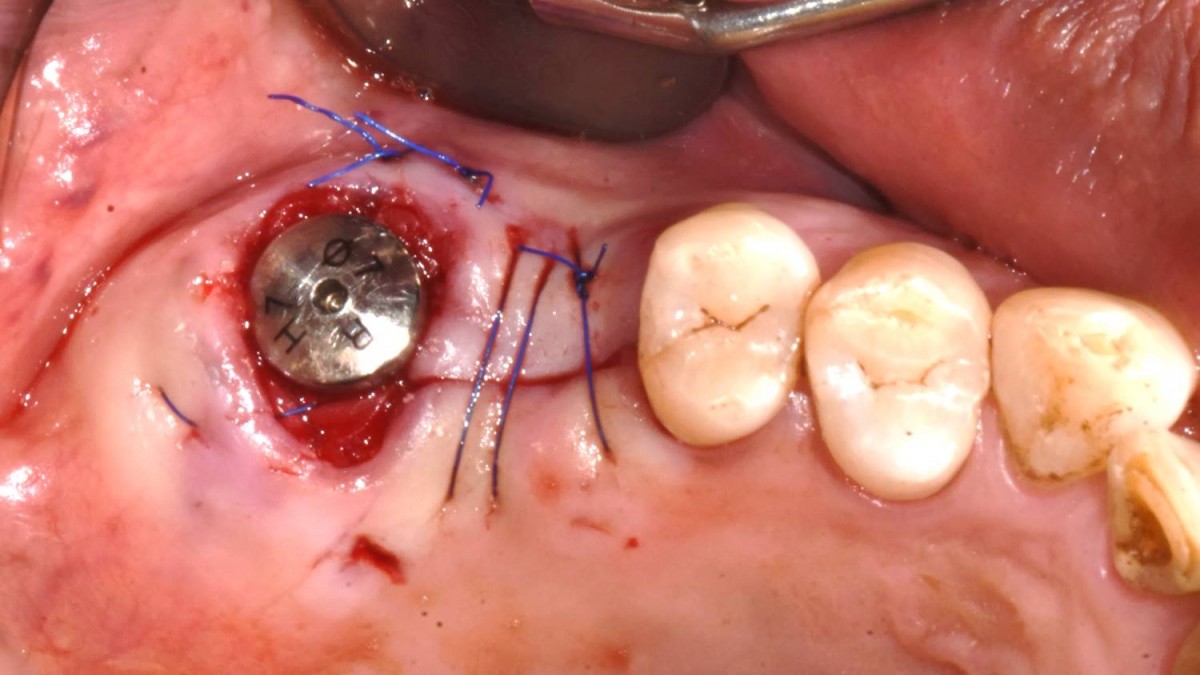

Maxillary Sinus Graft, 2 Implants, Crown Contouring

<GCaks> A 56-year-old male patient had pain-inducing caries, and perio-involved tooth mobility resulted in a tooth fracture at 1st molar. And it was removed months ago. He was a heavy smoker and showed poor oral hygiene.